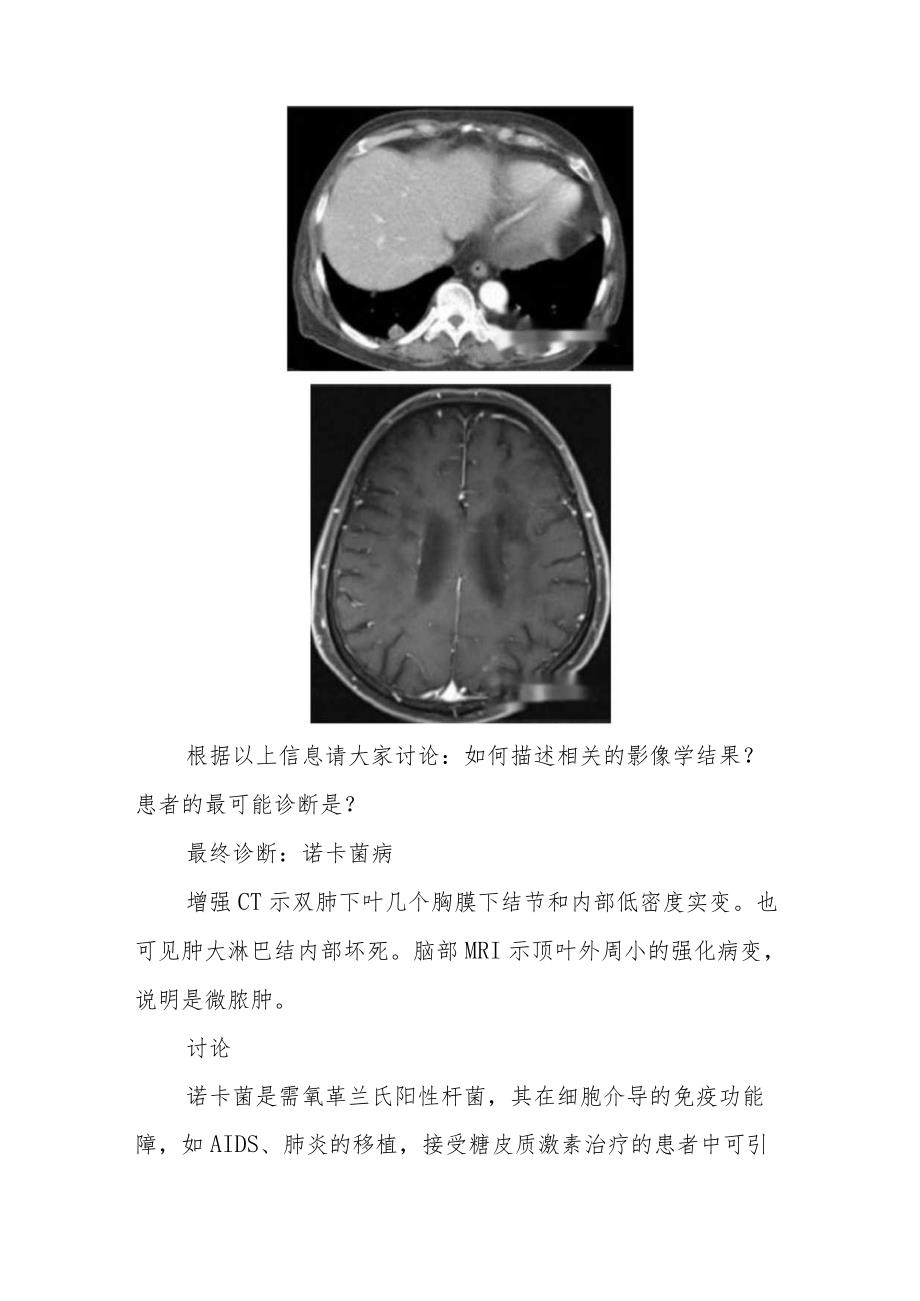

放射科医师晋升副主任医师病例分析专题报告单位:*姓名:*现任专业技术职务:*申报专业技术职务:*202*年*月*曰胸部CT异常病例分析病例分析专题报告男,76岁,腹部CT异常时偶见胸部CT异常,因肾病综合征使用糖皮质激素治疗6个月。以下为患者胸部和脑部影像学结果。根据以上信息请大家讨论:如何描述相关的影像学结果?患者的最可能诊断是?最终诊断:诺卡菌病增强CT示双肺下叶几个胸膜下结节和内部低密度实变。也可见肿大淋巴结内部坏死。脑部MRI示顶叶外周小的强化病变,说明是微脓肿。讨论诺卡菌是需氧革兰氏阳性杆菌,其在细胞介导的免疫功能障,如AIDS、肺炎的移植,接受糖皮质激素治疗的患者中可引起肺炎。肺奴卡菌病出现的体征和症状类似肺结核如发热,冷颤,疲劳,呼吸困难,咳嗽,咯血,盗汗,体重减轻。播散性诺卡菌病发生血行播散,从肺部,最常播散至中枢神经系统,皮肤,关节。在胸部CT上,多发性肺部实变有低衰减,并且主要病变部位可能有空洞。奴卡菌病也可以表现为结节及肿块,由于病变延伸可累及胸膜或胸壁。鉴别诊断肺奴卡菌病的鉴别诊断包括引起肺实变,空洞和结节的其他原因,如感染,血管炎,和恶性肿瘤。放线菌病可以和诺卡氏菌有相似的CT表现,但放线菌病不能播散至中枢神经系统。治疗肺奴卡菌病的治疗是磺胺类抗生素,可以行外科手术或引流治疗广泛的肺损伤。